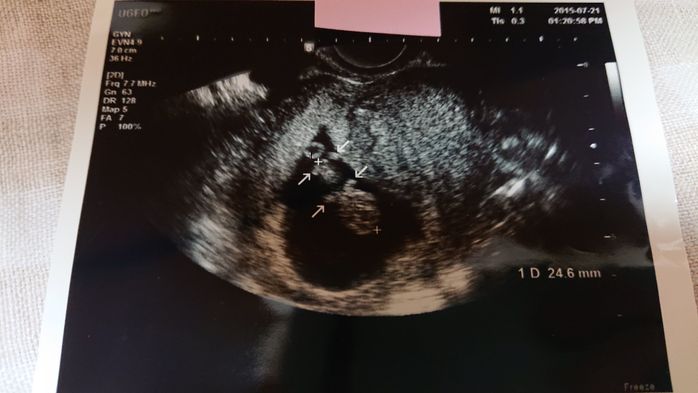

《妊娠9週目のエコー写真》

前回のエコー検査から2週間が経った妊娠9週での健診。この2週間で医師もびっくりするくらい赤ちゃんが大きくなりました。「急に大きくなりすぎて予定日が確定しがたいな~」と告げる医師。3月上旬くらいという話だった予定日が、2月20日ごろに変更となりました。小さな小さな手足もできていて「人っぽくなってきた」と赤ちゃんの存在をより実感した1枚です。矢印の部分が手足です。